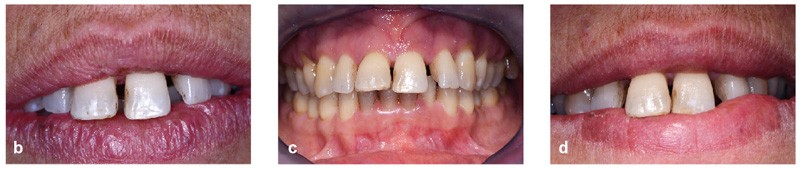

Bien souvent, dans les formes sévères, la diminution du boîtier osseux entraîne la migration et le déplacement de dents et notamment dans le secteur antérieur. Ces migrations ont un aspect disgracieux qui amène bon nombre de patients à consulter un orthodontiste pour corriger ces malpositions et retrouver à la fois une esthétique du sourire plus agréable et une fonction masticatrice plus efficace. Cependant, l’origine de ces migrations tient à l’inflammation du parodonte se traduisant par une plus grande laxité ligamentaire et une destruction du boîtier osseux. Dans certains cas, une surcharge occlusale aggrave encore le déplacement. Le traitement de l’inflammation par une thérapeutique initiale parodontale diminue la migration mais souvent, ne suffit pas à retrouver un positionnement correct (fig. 1). Il est alors nécessaire de mettre en œuvre une prise en charge orthodontique.